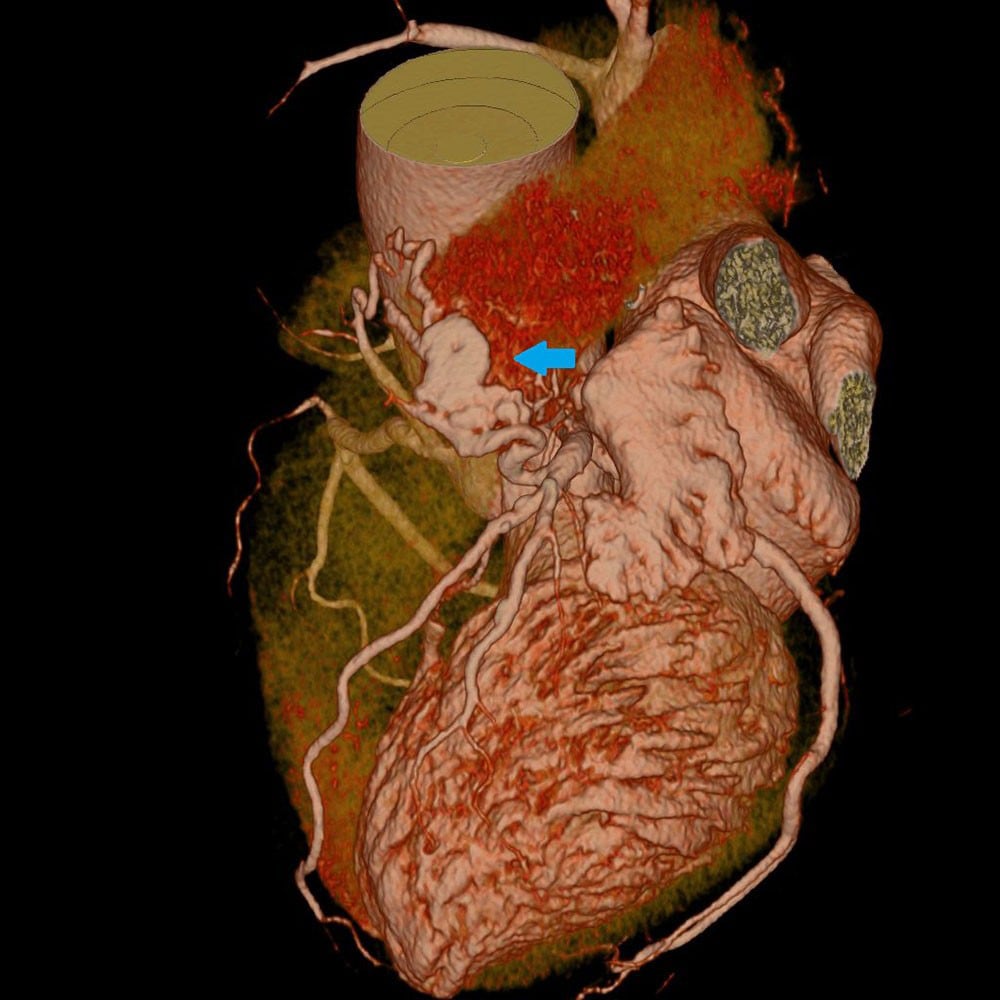

図1.心臓CT(VR)

冠動脈CTにて右冠動脈肺動脈瘻を認める。

図2.心臓CT(VR)

冠動脈CTにて左冠動脈肺動脈瘻を認める。

今回の症例では、冠動脈CTで冠動脈肺動脈瘻が見つかったがCAGを行うことで各冠動脈を造影することでRCA→Lt.PA、LCA→Lt.PAへfistula、LCAからのfistulaにはaneurysmφ5-7mmがあることがわかりより詳細な情報が得られた。